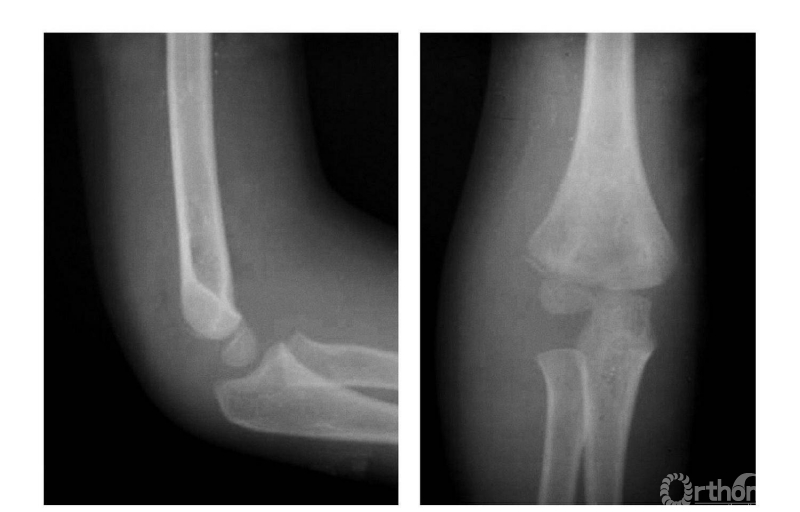

二、尺偏型

例:见肱骨小头及滑车骨骺伴前臂骨一同移向肘之尺侧,并略有旋转(图2)。

图2